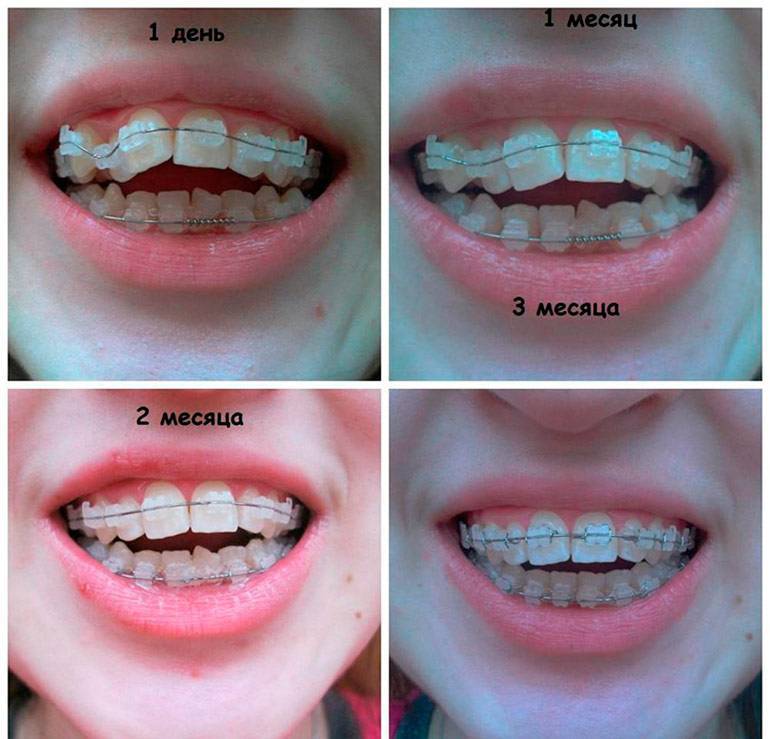

Брекеты ставят детям, как правило, на несколько лет